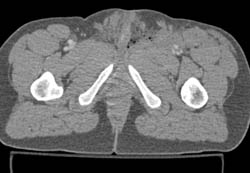

Diagnosis

Non Union